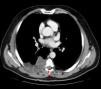

Clinical ObservationA 52-year-old man, with no medical history of interest, presented with a 6-month history of dorsal thoracic pain. As the patient's symptoms did not improve, it was decided to perform magnetic resonance imaging (MRI), following a normal chest radiograph. The diagnosis was costal hydatidosis with intraspinal extension (Fig. 1). Due to questions about the nature of this process, a thoracoabdominal computed tomography (CT) scan was requested, in which an 88mm×60mm×95mm right paravertebral mass was found. It was predominantly cystic with lobulated contours, extrapleural morphology and protruded through the right foramen between the sixth and seventh costal arches towards the spinal canal, extending paravertebrally from the fourth to the seventh right posterior costal arches, involving the extrapleural fat and extending towards the dorsal muscles through the intercostal spaces, with no costal involvement. As a result, the new suspected diagnosis was soft tissue sarcoma (Fig. 2). Fine needle aspiration was carried out (non-diagnostic). Given the intraspinal finding of the mass, it was decided to use a combined neurosurgical and thoracic approach.